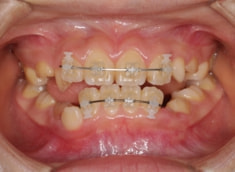

治療開始から11ヶ月

治療後(1年5ヶ月後)